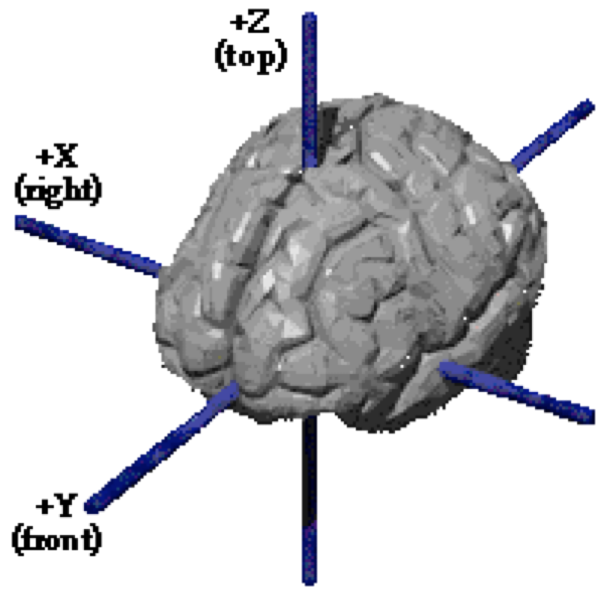

Templates and atlases are commonly used in neuroimaging research

There is significant lack of clarity in the use of these templates

Templateflow provides programmatic access to a database of templates and mappings between them

Easy to use for humans and machines:

Ciric et al., 2022, Nature Methods